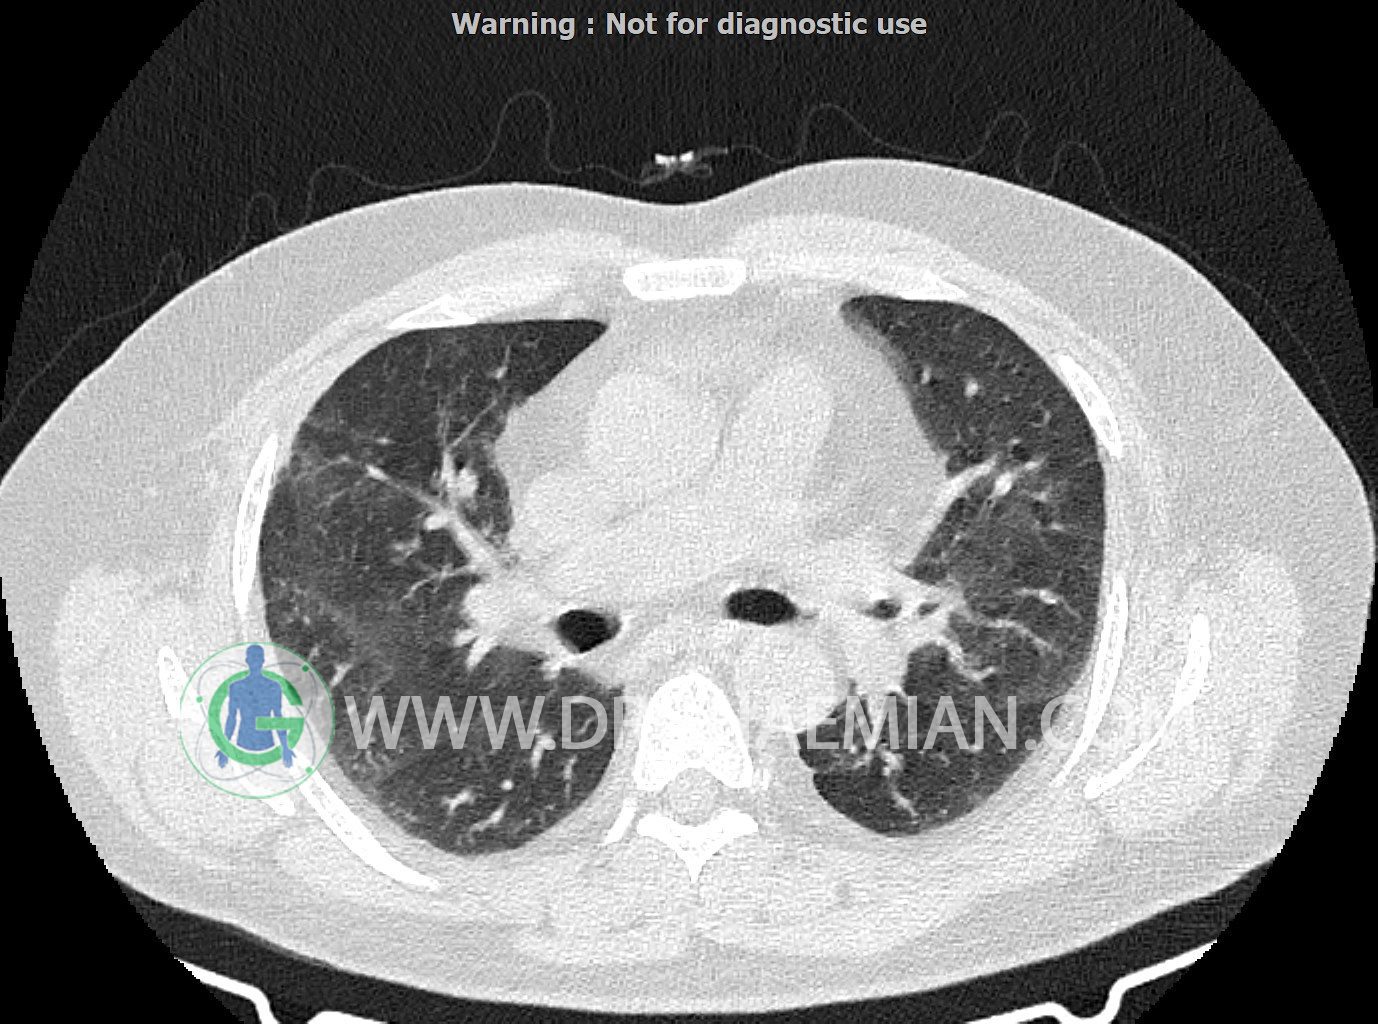

سی تی اسکن ریه یک روش تصویربرداری است که با استفاده از تشعشعات تصاویر عرضی مقطعی از ریه و بالا تنه ایجاد می کند. در این کیس کاردیومگالی،باندهای آتلکتازی و فیبروتیک پراکنده،کدورت های گراند گلاس،زمینه ی ادم قلبی (مراحل اولیه)،مشهده میشود.

حجم ریه ها، طرح برونکو واسکولر ریه ها، فیشر های دو طرف طبیعی است.

باندهای آتلکتازی و فیبروتیک پراکنده در دو طرف

peribronchial wall-thickening و عروق prominant در هیلوم دو طرف و کدورت های گراند گلاس دو طرفه

مشهود است.

شواهد فوق در درجه اول می تواند در زمینه ی ادم قلبی (مراحل اولیه) باشد.